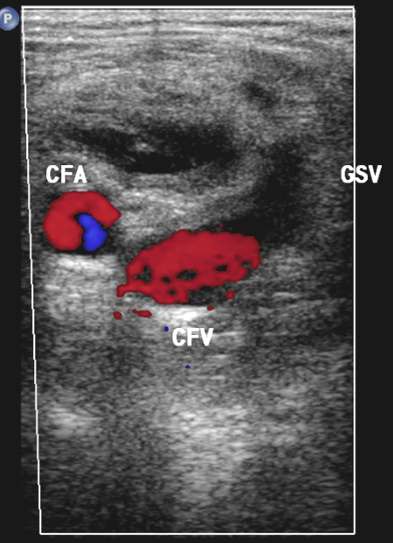

五、动静脉瘘 病例1:蛛网膜下腔出血,动脉瘤进行血管内弹簧栓子栓塞